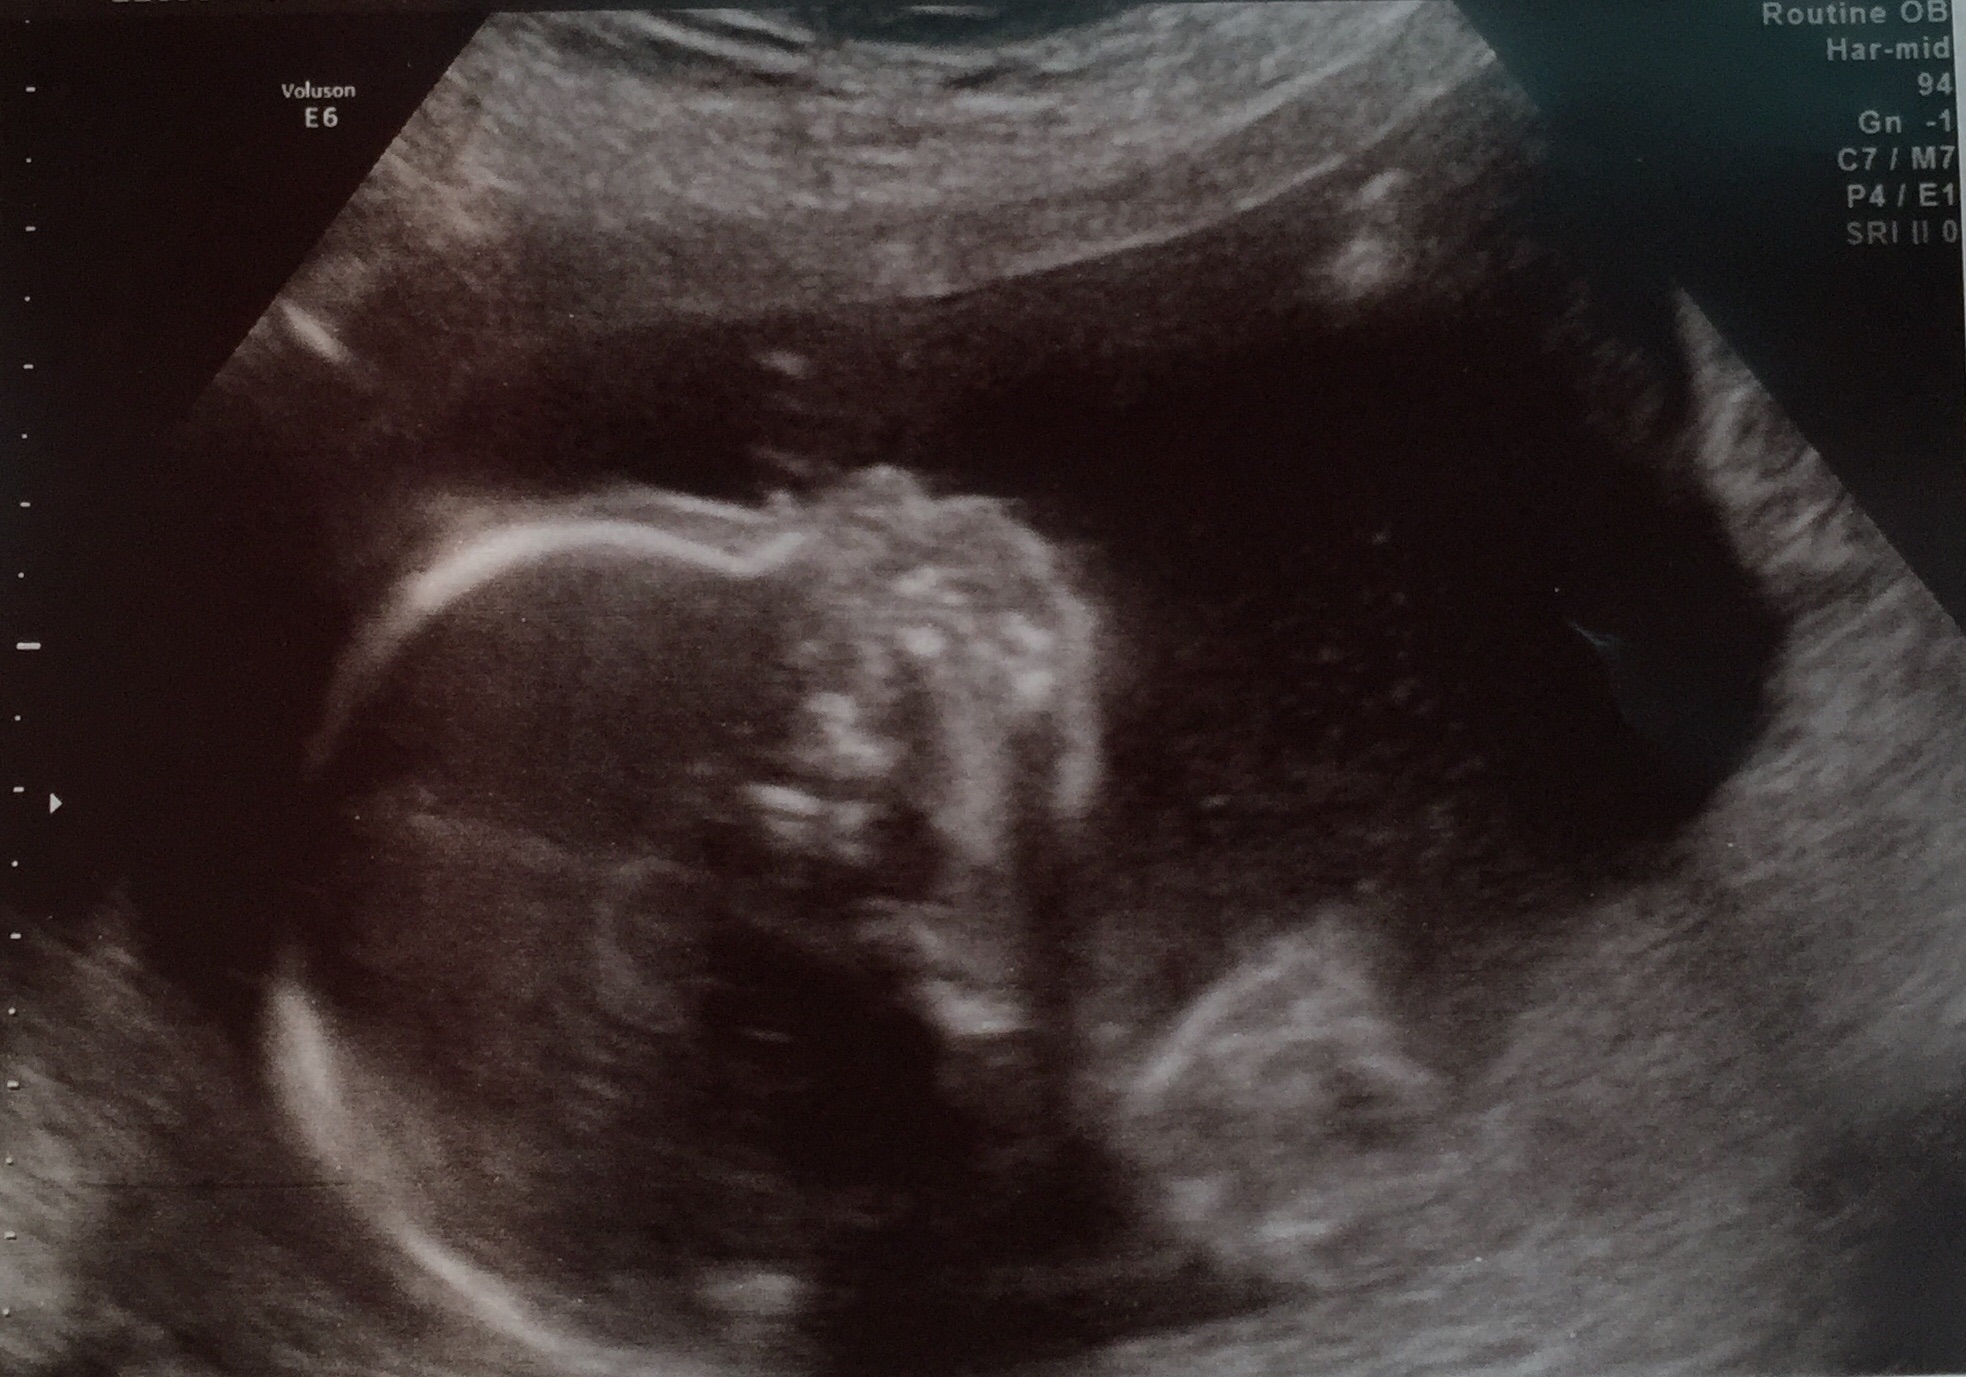

Me at 18w 1d which was monday. Had a/s Monday and will have cake tonight at dinner w friends for reveal. Can't wait! Here's a shot of baby too. Healthy as could be.